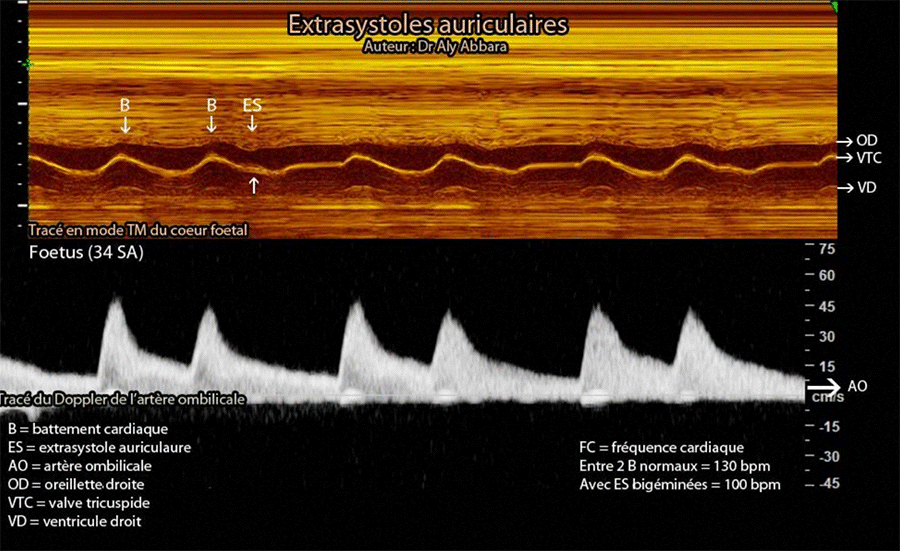

• Images échographiques analysant le tracé en mode TM du cœur fœtal comparé au tracé Doppler de l'artère ombilicale en cas de présence des extrasystoles bigéminées.

On remarque sur le tracé Doppler de l'artère ombilicale une arythmie cardiaque caractérisée par un allongement systématique du temps entre le 2e et 3e battements cardiaques normaux (comparé au temps séparant le 1e battement du suivant).

Cet allongement du temps est en rapport avec la survenue, suite au 2e battement cardiaque normal, d'un battement auriculaire prématuré (stimulation électrique auriculaire prématurée) ou " extrasystole auriculaire " (identifiable sur le tracé en mode TM du cœur fœtal et parfois sur le tracé en mode Doppler de l'artère ombilicale) ; cette extrasystole n'est pas suivi par un battement ventriculaire parce que, le ventriculaire est en phase réfractaire (durant laquelle, il ne répond pas aux stimulations).

La présence régulière et systématique d'une extrasystole auriculaire après le 2e battement cardiaque normal est à l'origine de ce bigéminisme (séries de deux battements cardiaques normaux séparés une extrasystole puis une pause compensatrice).

Il s'agit d'un fœtus de 34 SA, chez lequel l'échographie ne montre aucune anomalie cardiaque ni de retentissement dans ses fonctions, puis aucune anomalie morphologique et de croissance in utero